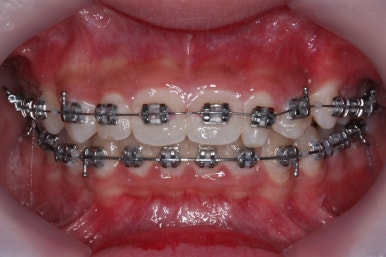

이정도면 다 끝난 것 같은 느낌이 드시지 않나요? 과개교합도 개선시켰고 매복치아 덧니도 가지런하게 했어요.

근데 문제는 지금부터였어요.

작은 앞니가 왜소치이다 보니 윗니에는 틈이 남아있고 교합도 조금 엉성한 모습이에요.

왜소치의 사이즈가 위아래 교합을 맞춰주는데 방해가 된다고 판단하여 왜소치를 크게 해주기로 결정했습니다.